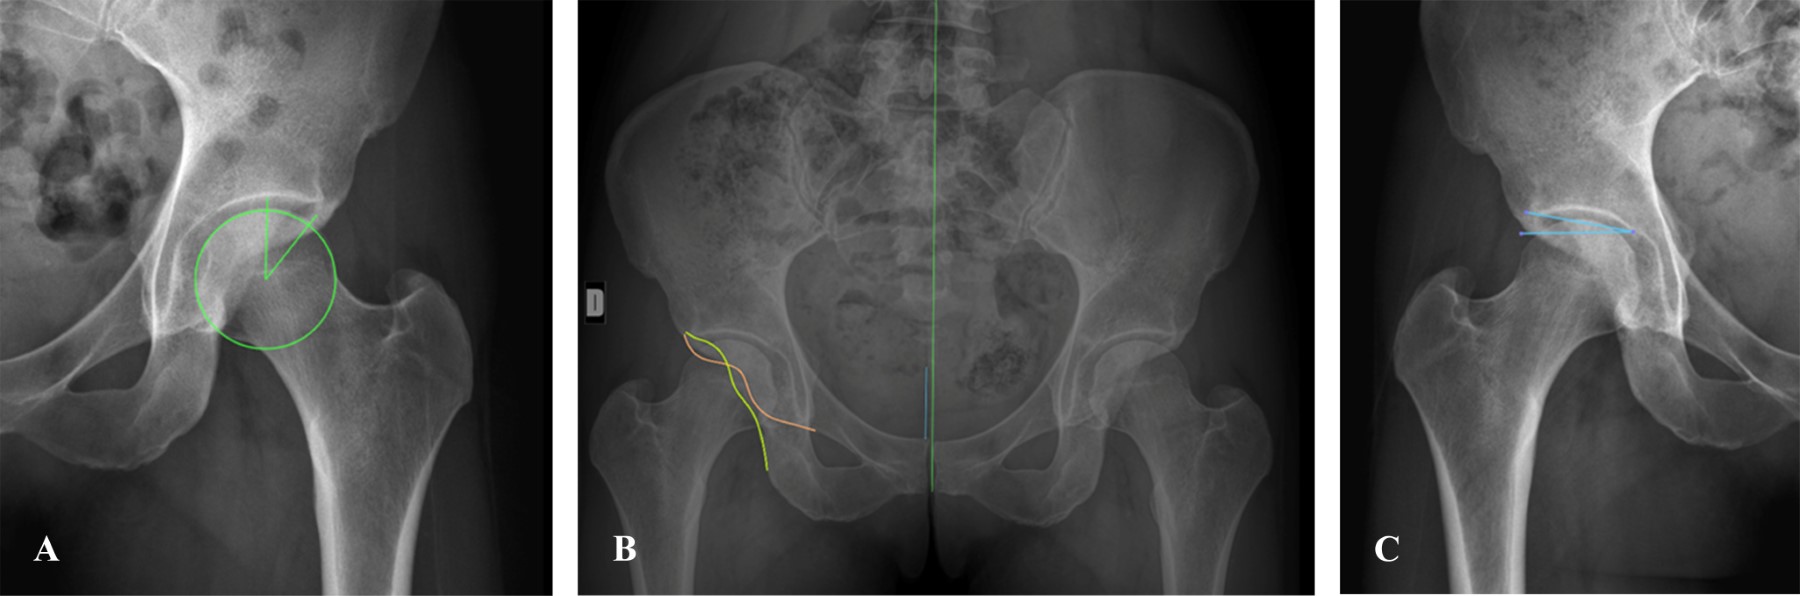

Figure 1

Figure 2

Figure 3

Figure 4

Figure 5

Figure 6

Figure 7

Figure 8

Figure 9

Figure 10

Figure 11

Figure 12

Figure 13

Figure 14